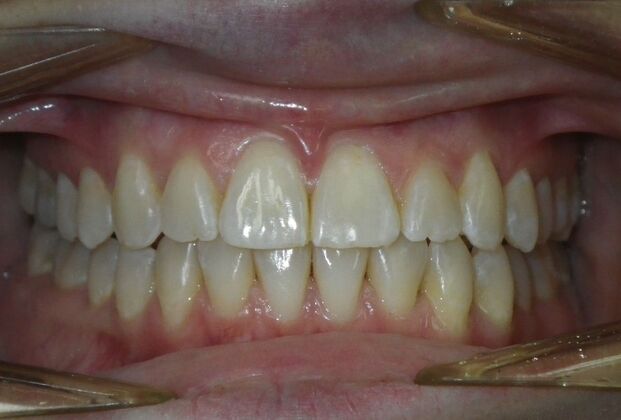

Invisalign: Case 18

This patient had concerns with the lower anterior teeth. There were some slight rotations and the midline of the lower incisors wasn't lined up with the upper midline. To correct this we used slenderizing of teeth in strategic areas of the lower arch to correct the rotations and line up the midlines. Patient very pleased with the results.